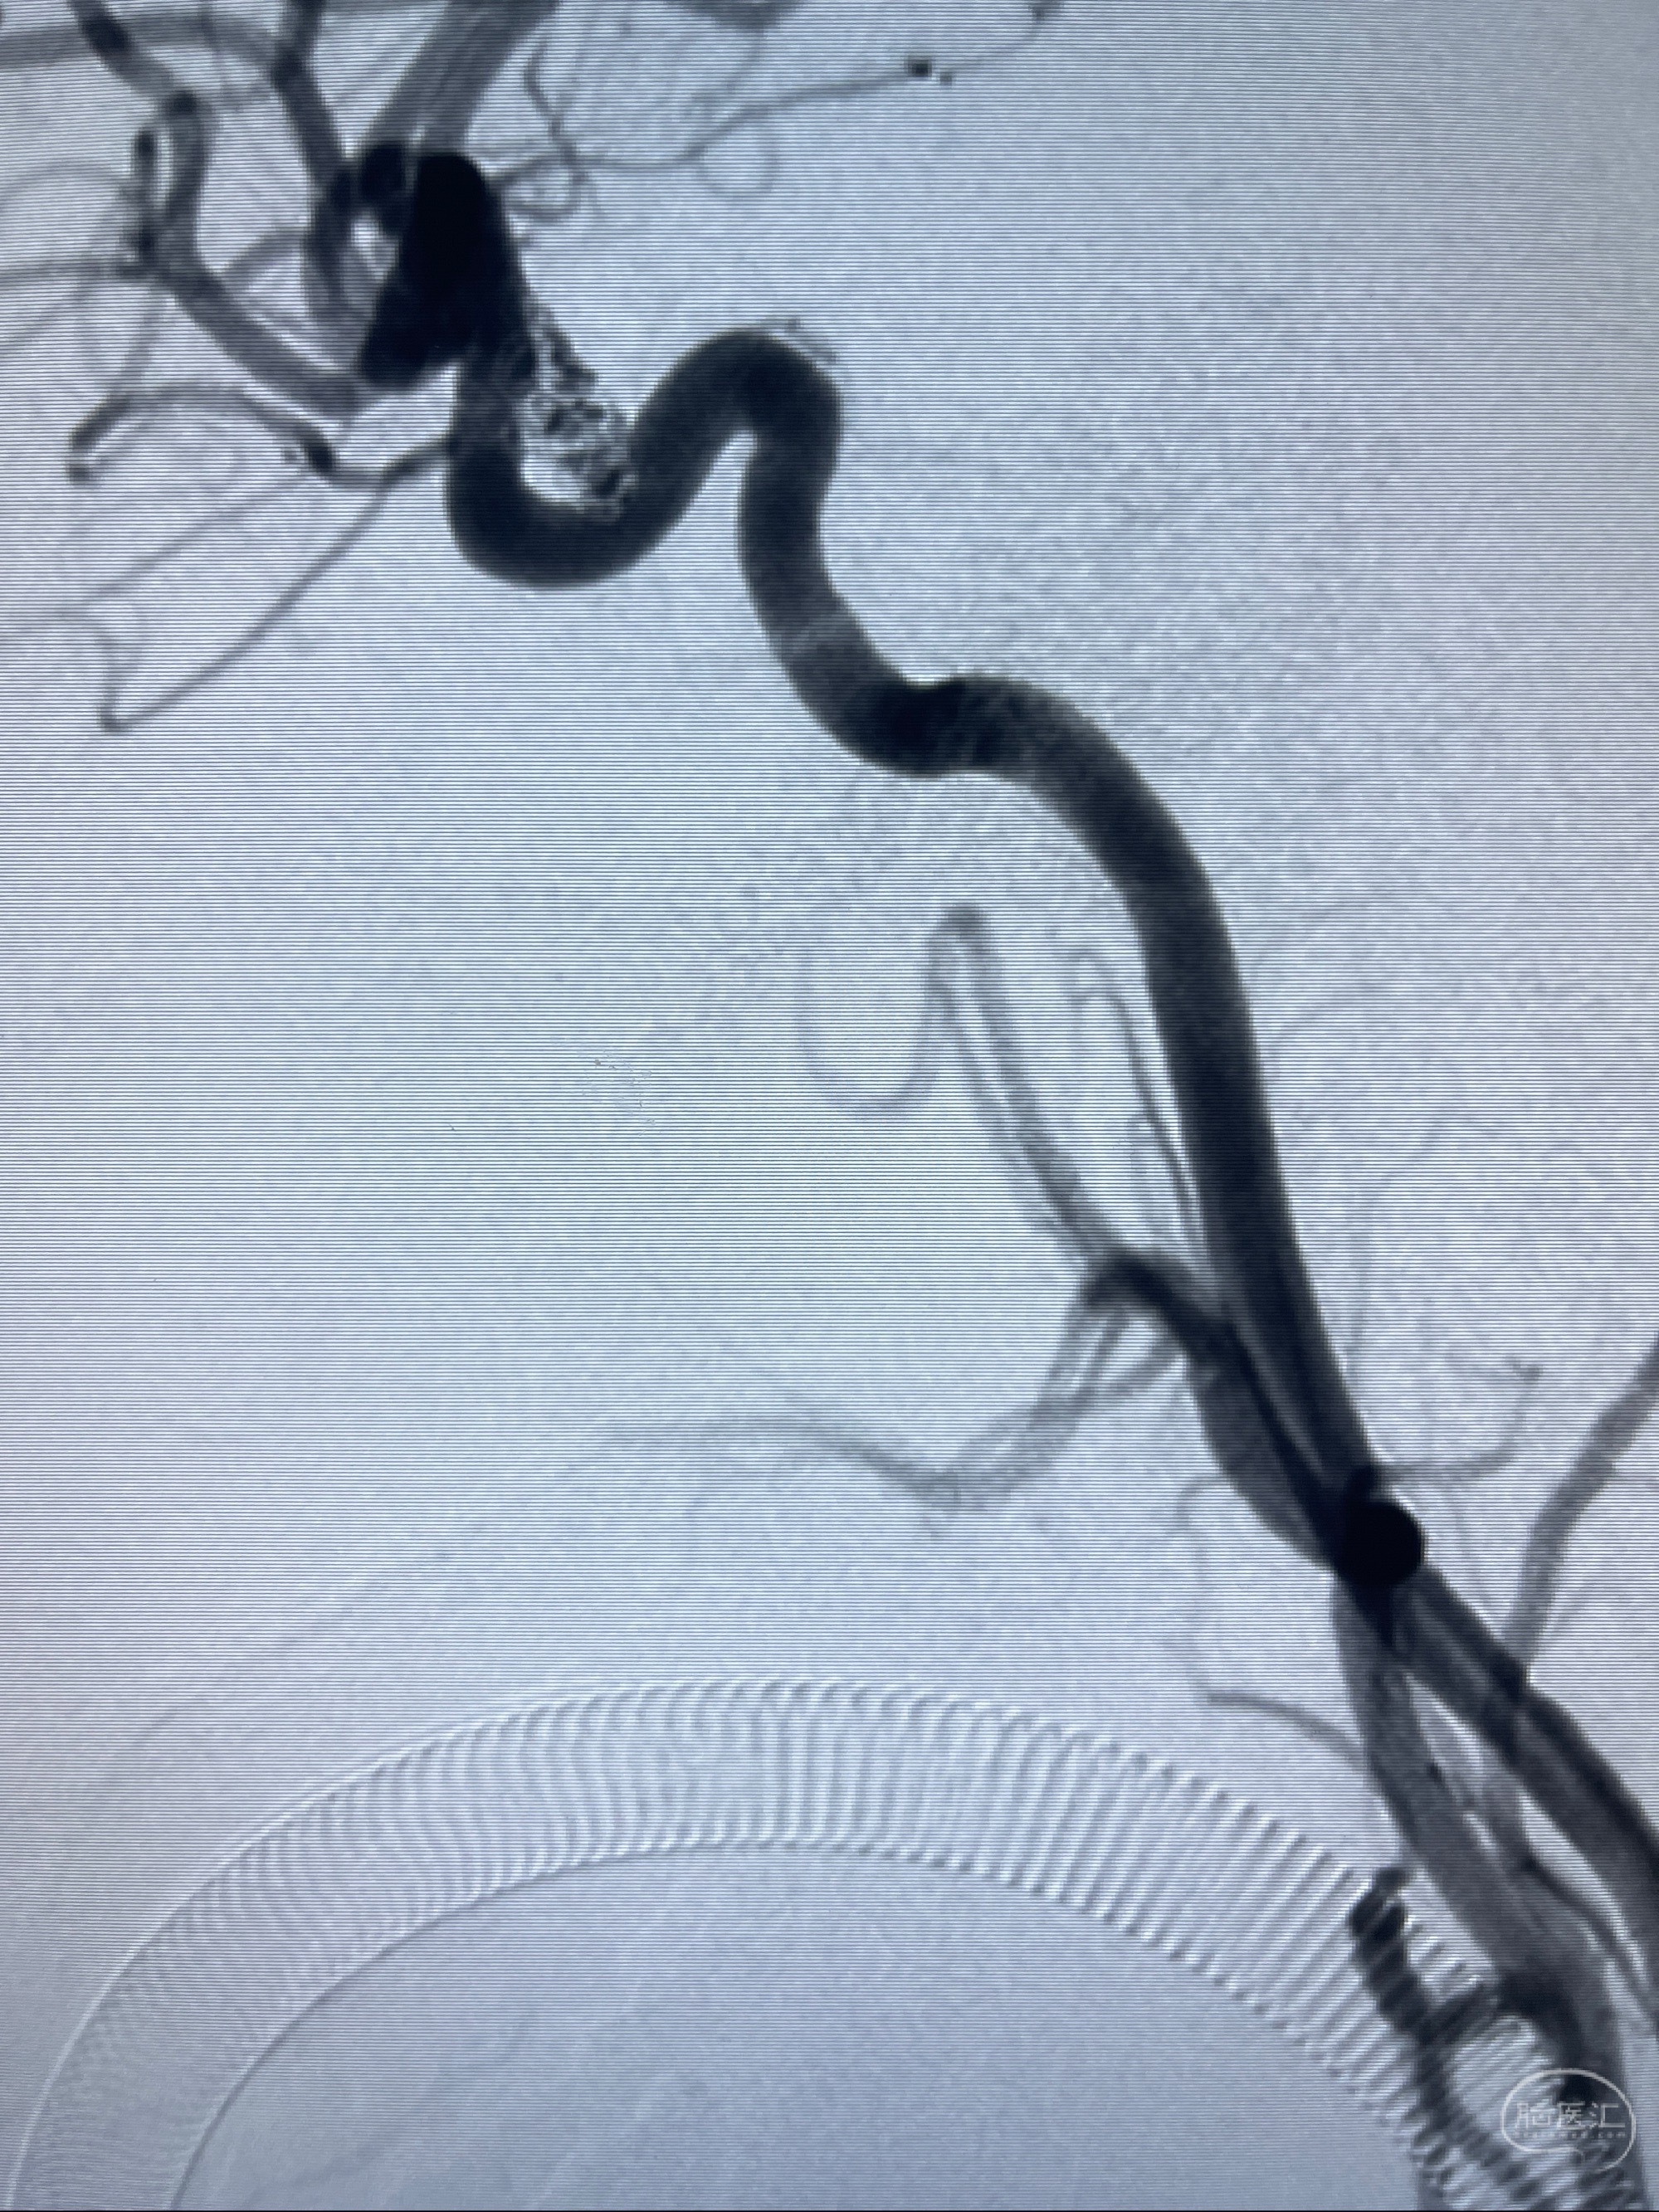

2023.07.25 泰州市人民医院查头颅CTA提示右侧C6段瘤样突起,建议DSA检查;

CTA示:右侧颈内动脉C6段见指向下方的突起,余左侧颈内动脉、双侧椎动脉、大脑前动脉、大脑中动脉、大脑后动脉及基底动脉走形正常,未见明显扩张及狭窄,局部未见明显瘤样扩张。

看原图,应该有两侧动脉瘤😅

2023-07-27全脑血管造影:双侧颈内动脉眼动脉段动脉瘤,右侧较大

2023-08-01全麻下行双侧颈眼动脉瘤支架辅助栓塞

- pipeling4.5-20mm

- pipeline 4.0-20mm